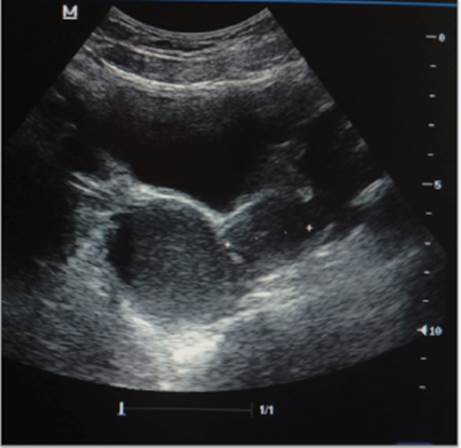

Escolar femenina de 11 años de edad, quien refirió menarquia a los 10 años y 6 meses, conocida con diagnóstico de agenesia renal izquierda, quien consultó por dismenorrea intensa. Al examen físico, en el abdomen había dolor en hipogastrio, el himen era anular, la vagina estaba permeable. En el ultrasonido 2D y 3D se apreció la presencia de útero doble: el útero izquierdo y la hemivagina izquierda (no comunicante) con hematómetra y hematocolpos, el útero derecho de aspecto normal (Figura 5).

Figura 5 Ecografía 2D. Paciente del caso número 3. Hemiútero izquierdo y hemivagina izquierda no comunicantes con hematómetra y hematocolpo.